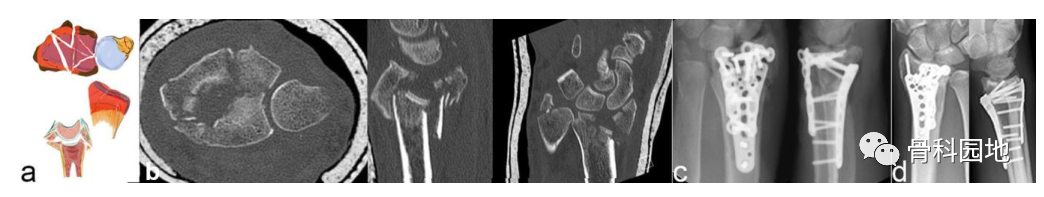

3、背侧关键骨块施加在背侧方向的作用力不仅会导致桡骨背侧骨折, 而且还会使腕关节背侧脱位。

注:背侧脱位,背侧外部插入。手掌韧带断裂(a)。普通 X 射线显示背侧脱位的程度。然而,在 CT 扫描中,可以看到关节面的额外凹陷、S 状切迹的台阶和背键骨块 (b)。背侧骨块不一定是关键骨块。如左两个图像所示。尽管背侧脱位,但掌侧骨折块仍附着在掌侧韧带装置上,这个由骨韧带组成的掌侧关键骨折块需要特别注意,必须首先固定,如图所示(c)